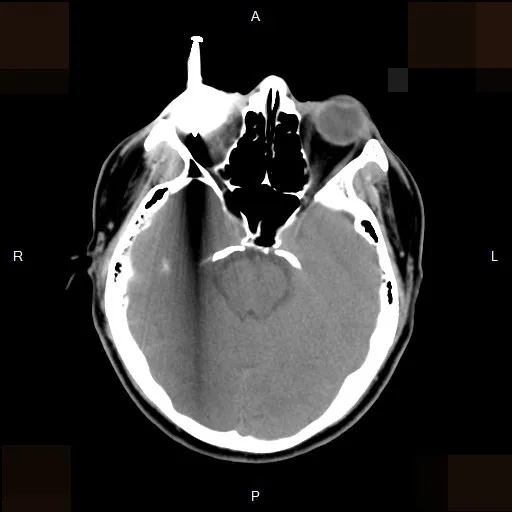

電腦斷層影像可看到男子右眼插著一根釘子,直達眼球的後方。李學宇醫師提供